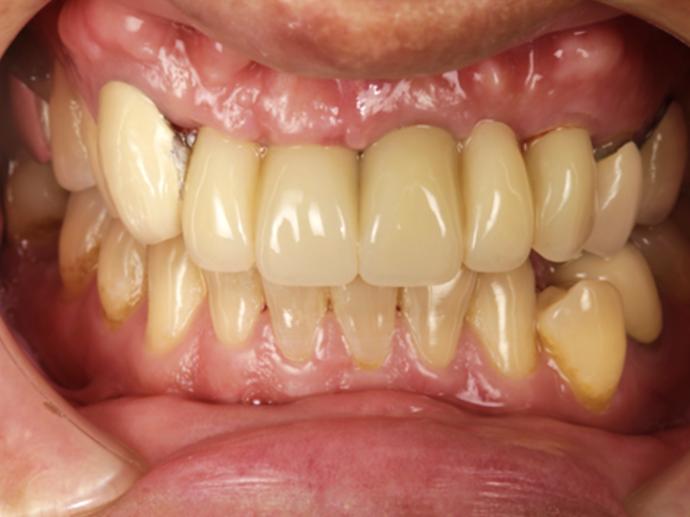

通過衛福部認證的專業技師,經由電腦設計及CADCAM數位先進製程,製作出堅固耐用、美觀自然的假牙。

美觀自然,提升生活品質與自信